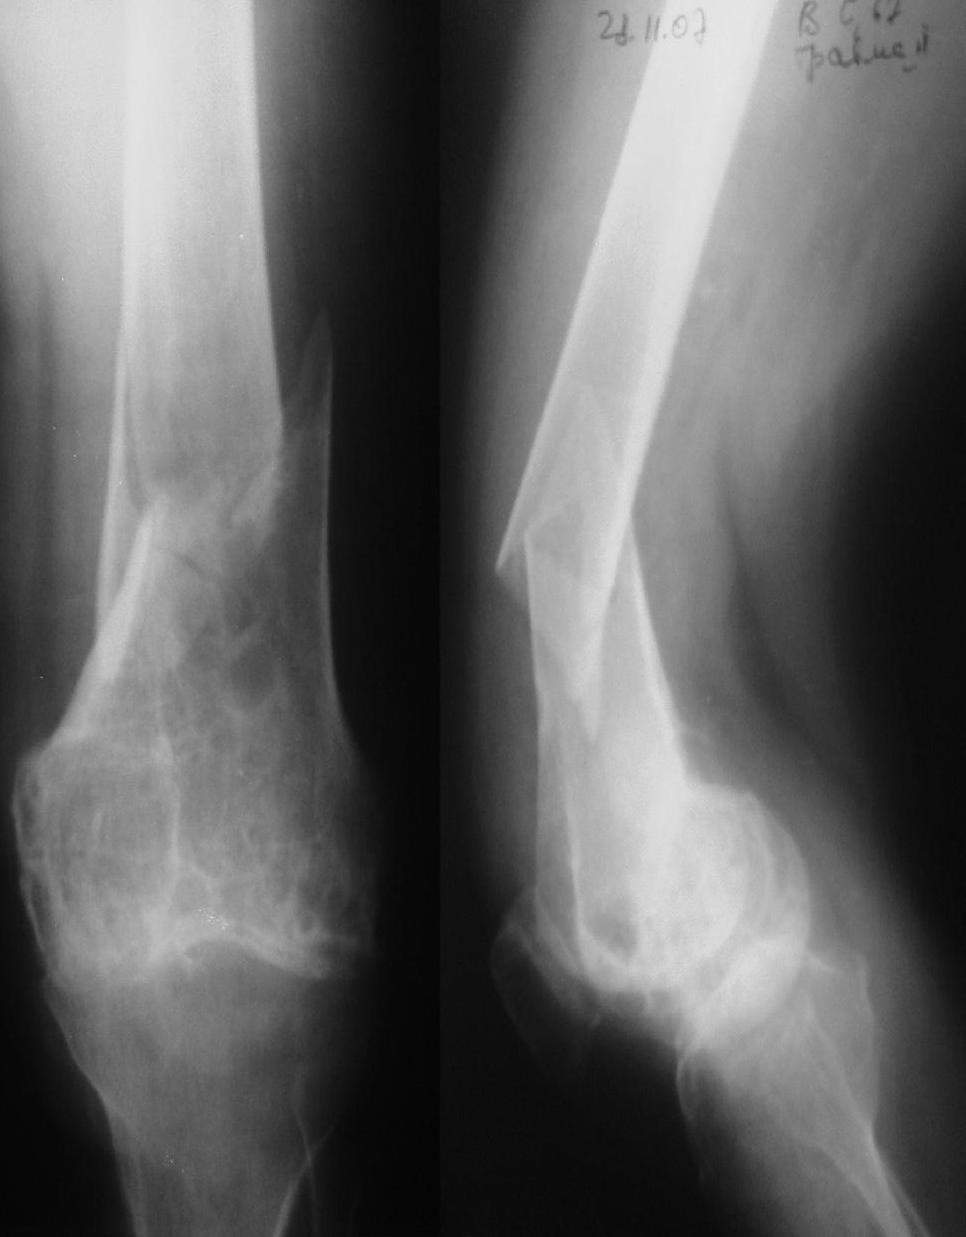

Пациентка 67 лет, поступила по скорой помощи с переломом левого бедра В 2003г оперирована по поводу рака молочной железы. В конце 2006 г появились боли в левом коленном суставе. На КТ бедра, со слов пациентки, выявлены метастазы в дистальный метаэпифиз бедренной кости. К сожалению самих снимков предоставить не может. В 2007 г, в июле больная получала курс химиотерапии. Коллеги, поделитесь вашими соображениями по поводу существующего процесса в бедре и дальнейшей тактики лечения. Заранее благодарю.